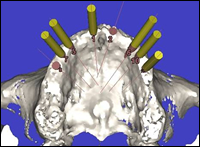

Fig 2 & 3: A DentaScan was taken to assess the maxilla in 3-dimensions. Eight dental implants were placed in the virtual image of the maxilla using Simplant software.